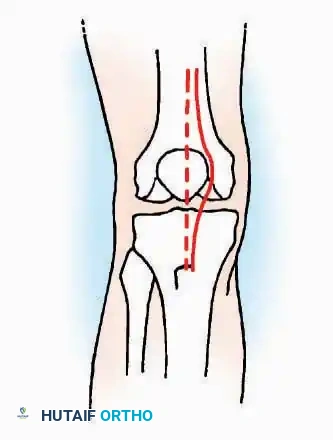

Anterior Approach

Indications: Total ankle arthroplasty (TAA), anterior ankle arthrodesis, and excision of anterior tibial/talar osteophytes (anterior impingement).

Surgical Technique:

* Incision: Make a 10 to 15 cm longitudinal incision over the anterior aspect of the ankle, centered exactly midway between the medial and lateral malleoli.

* Superficial Dissection: Incise the superficial fascia. Identify and protect the superficial peroneal nerve branches laterally and the saphenous nerve medially.

* Internervous Plane: The deep dissection exploits the plane between the Extensor Hallucis Longus (EHL) tendon (innervated by the deep peroneal nerve) and the Extensor Digitorum Longus (EDL) tendons (also innervated by the deep peroneal nerve).

* Neurovascular Bundle: Incise the extensor retinaculum. Carefully identify the anterior tibial artery and the deep peroneal nerve, which typically lie between the EHL and EDL, or directly deep to the EHL. Retract the neurovascular bundle laterally with the EDL, or medially with the EHL, depending on the specific anatomical variant encountered (lateral retraction is most common).

* Capsulotomy: Incise the anterior joint capsule longitudinally. Elevate the capsule subperiosteally from the anterior tibia and the talar neck to expose the entire tibiotalar articulation.